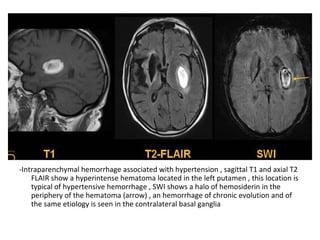

9-Hemorrhage :

-Hemorrhagic transformation is a little variably

used and collectively refers to two different

processes which have different incidence ,

appearance and prognostic implications ,

these are :

a) Petechial hemorrhage

b) Intracerebral hematoma

a) Petechial hemorrhages :

-Usually appear as the name suggests , as tiny

punctate regions of hemorrhage often not able

to be individually resolved but rather resulting in

increased attenuation of the region on CT of

signal loss on MRI , although this petechial

change can result in cortex appearing near

normal it should not be confused with the

phenomenon of fogging seen on CT which occurs

2 to 3 weeks after infarction

-Petechial hemorrhage typically is more

pronounced in grey matter and results in

increased attenuation

-This sometimes mimics normal grey matter

T1 , Hemorrhagic transformation is detected as areas of increased

signal intensity , the gyral pattern of increased signal intensity may

also represent cortical laminar necrosis

signal intensity